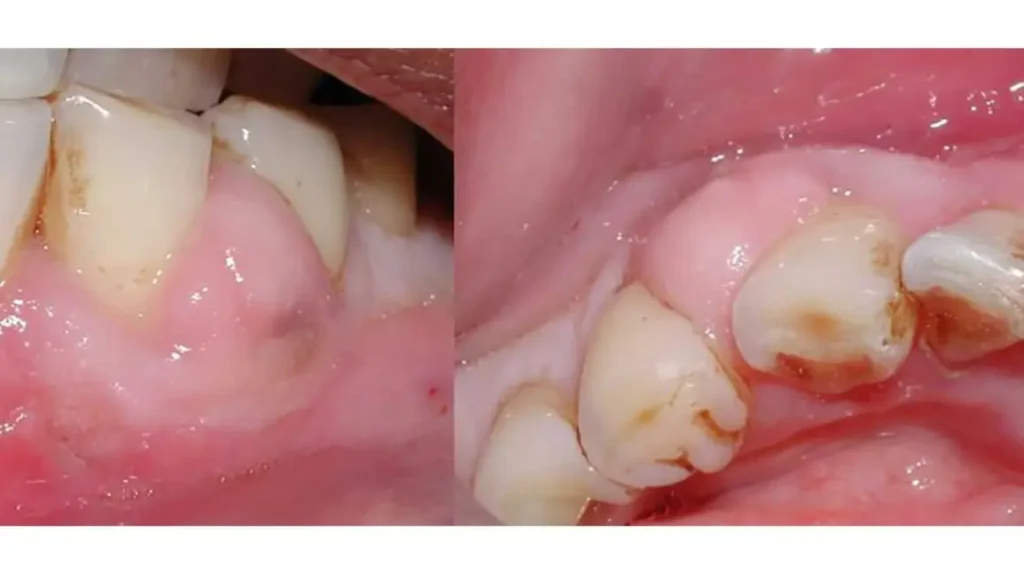

Gum Infections – Causes, Symptoms, and Best Treatment Options

What Is a Gum Infection? Dental health management plays a key role in one’s general health condition. Gum infections constitute one of the greatest dental problems Australians experience, and when untreated, can seriously harm oral health enough to lead to tooth loss. According to the Australian Institute of Health and Welfare (AIHW), in 2017–18, approximately […]